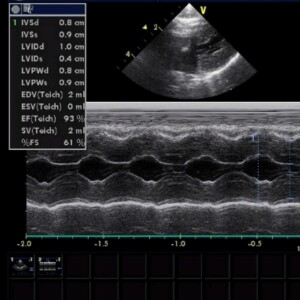

Окончательный диагноз ставится на основании ультразвукового исследования сердца (ЭХО КГ).